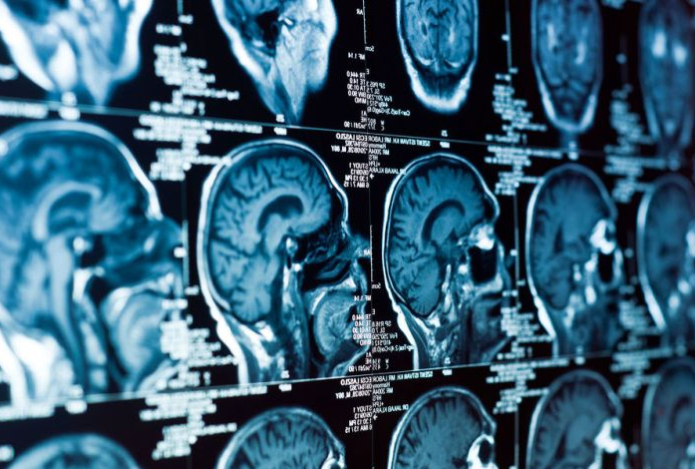

Анализ более 2600 МРТ-сканов мозга людей в возрасте от 30 до 97 лет позволил ученым проследить, как мозг трансформируется с возрастом, и как это соотносится с результатами когнитивных тестов. Выяснилось, что изменения формы мозга происходят неравномерно: одни области сжимаются, другие — расширяются, и у людей с признаками когнитивного снижения эти искажения выражены сильнее.

«Мы обнаружили, что трехмерная форма мозга систематически меняется с возрастом, и эти изменения глубоко влияют на память и способность к рассуждению», — объясняет нейробиолог Нильс Янссен из Университета Ла-Лагуна.

Особое внимание исследователи обратили на энторинальную кору — область мозга, играющую ключевую роль в регуляции памяти. Энторинальная кора при болезни Альцгеймера поражается одной из первых. По мнению ученых, возрастные изменения формы мозга могут оказывать давление на эту уязвимую зону, создавая условия для накопления токсичных белков и повреждений.

«Если стареющий мозг деформируется таким образом, что энторинальная кора оказывается „зажатой“, это может объяснить, почему именно она становится эпицентром патологии болезни Альцгеймера», — отмечает нейробиолог Майкл Ясса из UC Irvine.

В перспективе исследование может изменить подход к диагностике нейродегенеративных заболеваний. Авторы подчеркивают, что понимание геометрии мозга может сыграть ключевую роль в раннем выявлении деменции, а не только в оценке ее последствий.